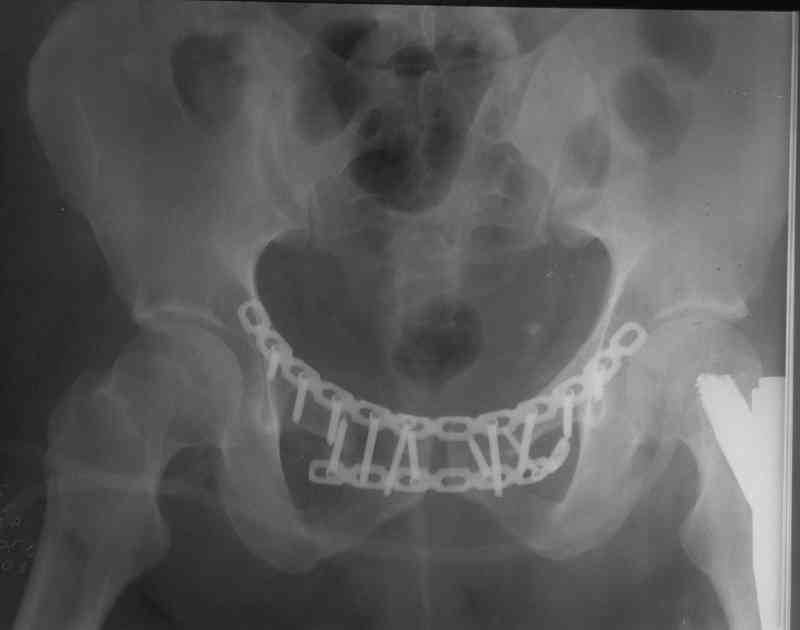

> метод фиксации таза: стержневой аппарат (тазового набора Илизарова нет в округе)

> каннюлированными винтами,

> передняя фиксация пластиной правого крестцово- подвздошного сочленения

Пластина спереди (на лонные кости) открыто и каннюлированные винты с обеих сторон сзади - закрыто.

Предварительная репозиция может быть достигнута при помощи аппарата.